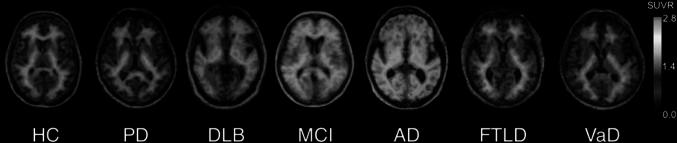

As a biomarker of beta-amyloid, positron emission tomography (PET) amyloid imaging offers a unique opportunity to detect the presence of this protein in the human body during life. Besides Alzheimer's disease (AD), deposits of beta-amyloid in the brain are also present in other neurodegenerative diseases associated to dementia, such as Parkinson's disease and dementia with Lewy bodies, as well as in other processes affecting brain function, such as cerebral amyloid angiopathy, brain trauma, Down's syndrome and meningiomas, as shown by post-mortem pathology studies. Furthermore, in systemic amyloidosis other organs besides the brain are affected, and amyloid PET imaging may be suitable for the identification of these extra-cerebral amyloid depositions. Finally, the potential use of amyloid PET tracer accumulation in cerebral white matter (WM) as a marker of myelin is being investigated, leading to some promising results in patients with WM lesions and multiple sclerosis. In this article, a review of the ongoing research pointing to a broader application of amyloid PET imaging in clinical practice beyond AD is provided.

作为β-淀粉样蛋白的生物标志物,正电子发射断层扫描(PET)淀粉样蛋白成像提供了一个独特的机会,可在活体中检测人体中这种蛋白质的存在。除阿尔茨海默病(AD)外,大脑中β-淀粉样蛋白沉积也存在于其他与痴呆相关的神经退行性疾病中,如帕金森病和路易体痴呆,以及其他影响脑功能的过程中,如脑淀粉样血管病、脑外伤、唐氏综合征和脑膜瘤,尸检病理学研究已证实这一点。此外,在系统性淀粉样变性中,除大脑外的其他器官也会受到影响,淀粉样蛋白PET成像可能适用于识别这些脑外淀粉样蛋白沉积。最后,正在研究将淀粉样蛋白PET示踪剂在脑白质(WM)中的积聚作为髓鞘标志物的潜在用途,这在患有WM病变和多发性硬化症的患者中已取得了一些有前景的结果。本文对正在进行的研究进行综述,这些研究表明淀粉样蛋白PET成像在临床实践中的应用范围将超越AD而得到更广泛的应用。